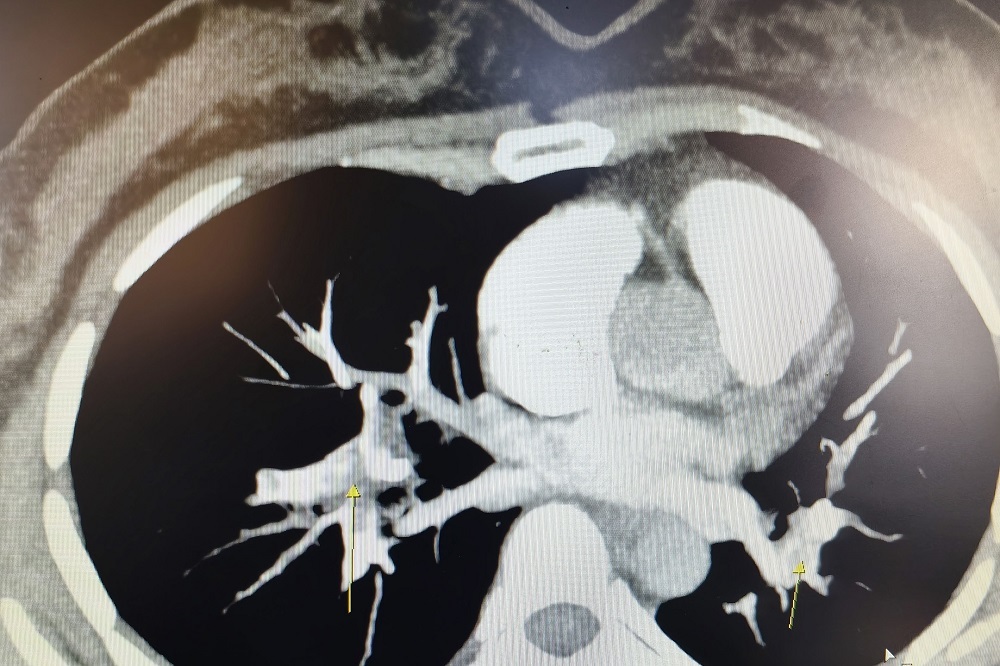

“急诊CT提示,患者肺部双侧与主干血管均有不同程度的栓塞,我们立刻采取了吸氧、抗凝等治疗。”台州玉环市人民医院呼吸与危重症医学科主治医师王剑解释,彭女士是因久坐导致下肢深静脉血栓,引起急性肺栓塞、呼吸衰竭。

CT影像